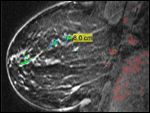

This case demonstrates the benefit of multimodality imaging including digital mammography and breast magnetic resonance imaging (MRI) in this patient, which led to a diagnosis of ductal carcinoma in situ (DCIS). There has been some conflicting information in the literature regarding MRI and its usefulness in the evaluation of DCIS. For this patient, the MRI revealed the extensive area of involvement more so than mammography. This information was critical to the surgeon for surgical planning.